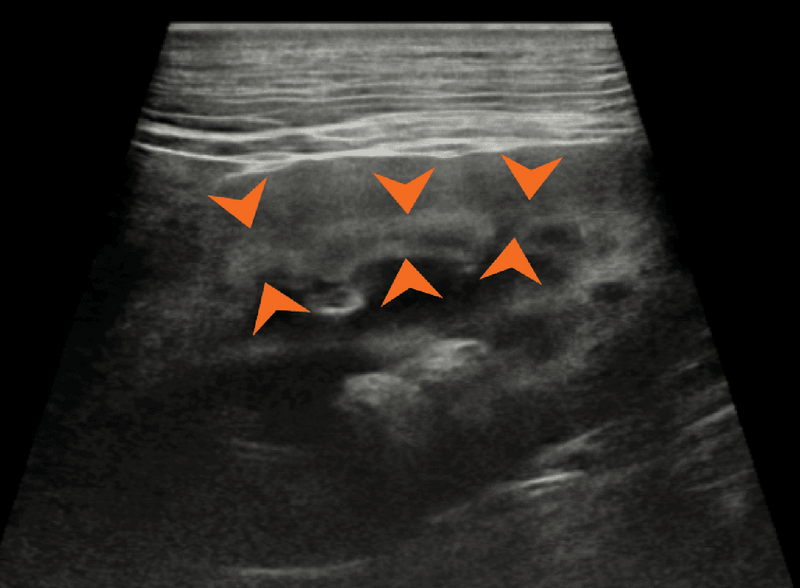

Ryc. 2. Obraz w projekcji strzałkowej prawidłowej lewej nerki psa, ukazujący hiperechogeniczny zewnętrzny pas rdzeniowy (groty strzałek).